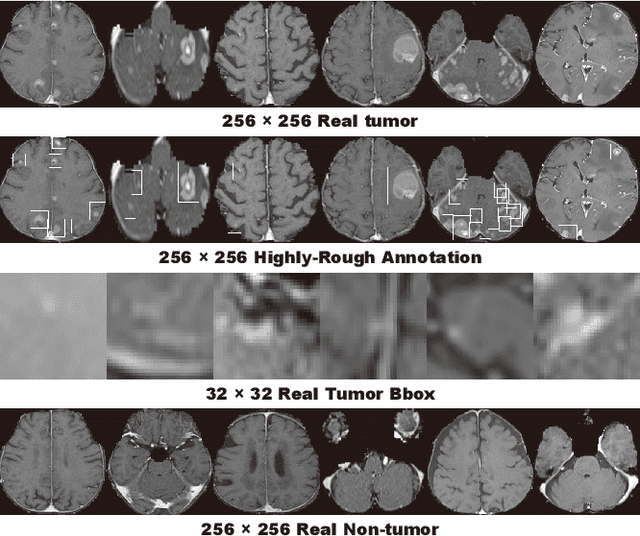

Abstract:Accurate computer-assisted diagnosis can alleviate the risk of overlooking the diagnosis in a clinical environment. Towards this, as a Data Augmentation (DA) technique, Generative Adversarial Networks (GANs) can synthesize additional training data to handle small/fragmented medical images from various scanners; those images are realistic but completely different from the original ones, filling the data lack in the real image distribution. However, we cannot easily use them to locate the position of disease areas, considering expert physicians' annotation as time-expensive tasks. Therefore, this paper proposes Conditional Progressive Growing of GANs (CPGGANs), incorporating bounding box conditions into PGGANs to place brain metastases at desired position/size on 256 x 256 Magnetic Resonance (MR) images, for Convolutional Neural Network-based tumor detection; this first GAN-based medical DA using automatic bounding box annotation improves the robustness during training. The results show that CPGGAN-based DA can boost 10% sensitivity in diagnosis with an acceptable amount of additional False Positives---even with physicians' highly-rough and inconsistent bounding box annotation. Surprisingly, further realistic tumor appearance, achieved with additional normal brain MR images for CPGGAN training, does not contribute to detection performance, while even three expert physicians cannot accurately distinguish them from the real ones in Visual Turing Test.